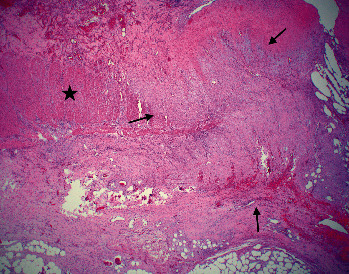

Inflammatory myofibroblastic tumor (IMT) is a rare mesenchymal tumors of unknown etiology composed of myofibroblastic cells admixed with inflammatory cells. Presented is a 72-year-old male hospitalized for severe abdominal pain and hematochezia with onset of associated symptoms of fever and sweats a few hours prior to abdominal pain. A computed tomography (CT) demonstrated left colonic thickening interpreted as partial obstruction, gross adhesions, and ischemia. At surgery, marked bowel ischemia from the distal transverse to proximal sigmoid colon was seen with extensive gross adhesions. Histopathology revealed a mesenteric mass chiefly composed of stellate-to-spindled myofibroblastic cells and fibrous adhesions, intermixed with lymphocytes, histiocytes, and plasma cells. The tumor was positive for desmin, smooth muscle actin, and keratin; tumor staging, grade, and postsurgical follow-up were not completed as the patient expired postoperatively. Illustrated is a rare pathologic mimic of ischemic colitis with fibrous adhesions, IMT. Thus, it should not be assumed that fibrous adhesions are always the etiology of obstruction when "adhesions" between sections of bowel are noted radiologically or surgically.

Abstract Image